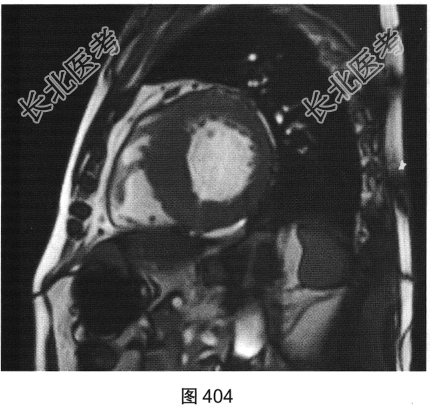

- [材料题] 患者男性,43岁,因“活动后胸痛3年”,外地医院拟诊梗阻性肥厚型心肌病,为明确诊断而转诊本院。

- 简答题3、患者超声心动图检查未能明确诊断,临床申请心脏磁共振检查,如图404~图408所示。患者心脏磁共振检查的异常征象有?